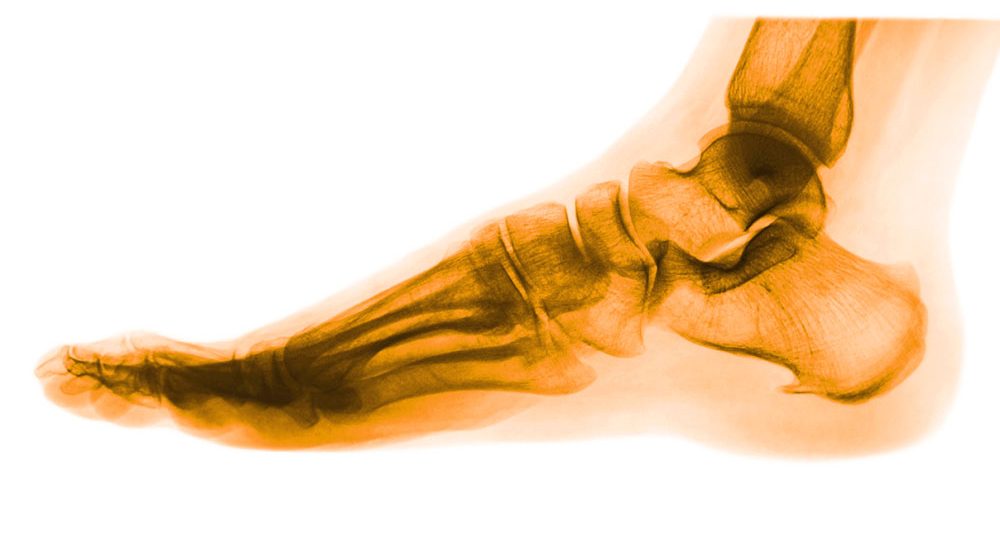

En nuestra clínica tratamos todo tipo de alteraciones en el pie, de una simple alteración en la piel hasta una deformidad morfológica. Realizamos estudios estáticos y biomecánicos, estudio de la marcha y de la postura.

Hacemos tratamientos conservadores como plantillas, siliconas, correcciones de las uñas, tratamientos no invasivos del dolor como ondas de choque y láser, tratamientos invasivos para el dolor como infiltraciones ecoguiadas,… y por último la cirugía del pie.